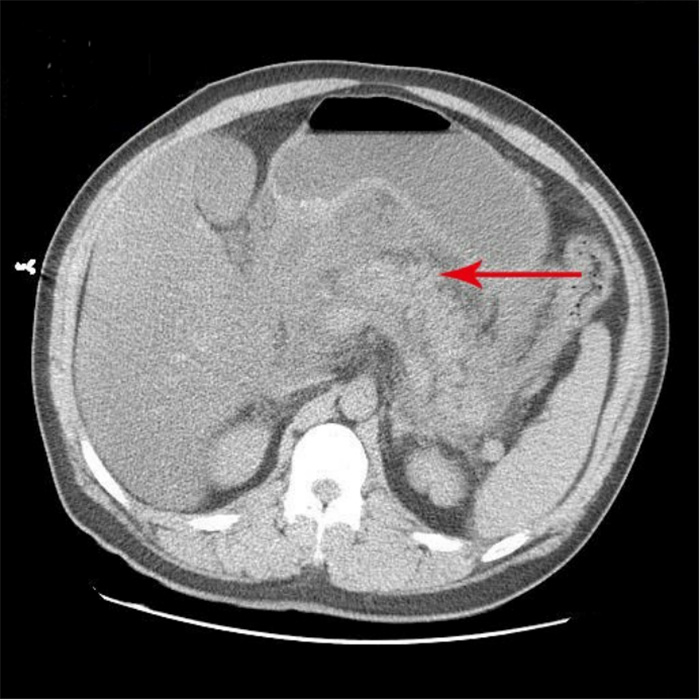

| 胆囊内可见高密度影,A:CT值为62 HU;B:CT值102 HU;C:胰腺假性囊肿引流管 图 2 入院第57天复查腹部CT |

患者病程41 d、57 d查腹部CT分别提示胆囊结石和胆囊内出血的可能性,这是患者入院腹部CT所没有的特征,检测胆囊内病灶CT值为62~102 HU。多学科会诊中大部分专家意见认为胆囊出血临床极罕见,胆囊内病灶并不考虑出血,仍考虑结石可能性大。因患者首次便血后给予对症治疗后便血症状停止,故没有选择血管造影进一步检查明确病因。

回顾总结该病例,不难发现,患者病程中两次活动性出血有共同点:先间断性右上腹痛,继之便血,伴γ-GT、CBil指标异常升高,以及胆囊内出现疑似结石、出血的影像学改变。胆囊内出血经胆道排出后,在十二指肠处可见少量新鲜血液,故首次胃镜检查时,根据十二指肠球部少量新鲜血迹判断球部炎症存在一定的误诊。另外,特别需要强调的是,少量的出血混合胆汁在影像学检查上表现为疑似新发的胆囊结石,临床不应直接考虑为胆囊淤胆性结石,尤其急性SAP患者出现上诉临床特征时,应当考虑胆囊动脉出血的可能性。直至患者第二次便血后,再次组织多学科会诊联合介入放射科进一步行血管造影,发现并确定胆囊动脉出血,但未见明显动脉瘤征象,行胆囊动脉栓塞后患者出血停止。